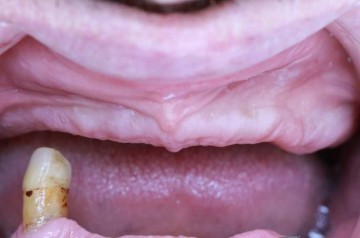

Пациент в возрасте 50 лет имел обширные проблемы с зубами, что привело к их полной потере, за исключением одного. Чтобы восстановить необходимую функциональность и эстетику улыбки, была проведена процедура установки коронки из высококачественного диоксида циркония для спасения последнего оставшегося зуба. В дальнейшем для пациента были изготовлены и успешно установлены съемные акриловые протезы как для верхней, так и для нижней челюсти.